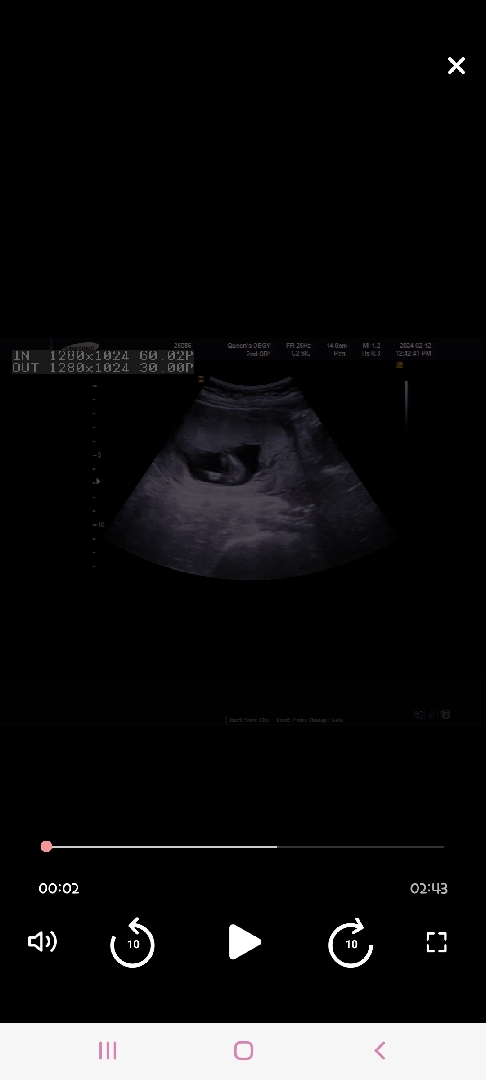

딸일까요??아들일까요?